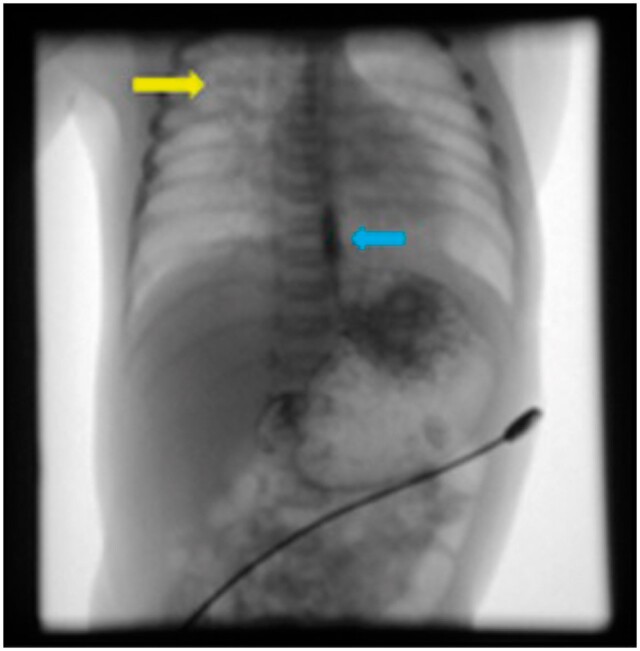

Intramural oesophageal dissection (IED) is an uncommon condition in newborns marked by the separation of the mucosal and submucosal layers of the oesophageal wall, both transversely and longitudinally, which may or may not involve perforation. A neonate presented at 26 h of life with poor respiratory effort and lethargy. She was intubated and was put on mechanical ventilation. Radiograph of the neonate suggested malpositioned endotracheal tube. The fluoroscopic dye-study indicated gastroesophageal oesophageal reflux disease and nothing significant. On limited CT contrast study of thorax, a tubular structure was seen running just parallel to the oesophagus extending from the T2 to the T9 levels. Possibilities of a oesophageal duplication/IED were considered. The neonate underwent an endoscopy and gastrostomy on day of life (DOL) 9. On follow up at 3 months a repeat limited CT study was done with instillation of water-soluble contrast. The previously seen tubular structure running parallel to the oesophagus was no longer seen. This finding suggested a healed IED. This case report emphasizes the significance of multimodality imaging in the diagnosis of this condition.